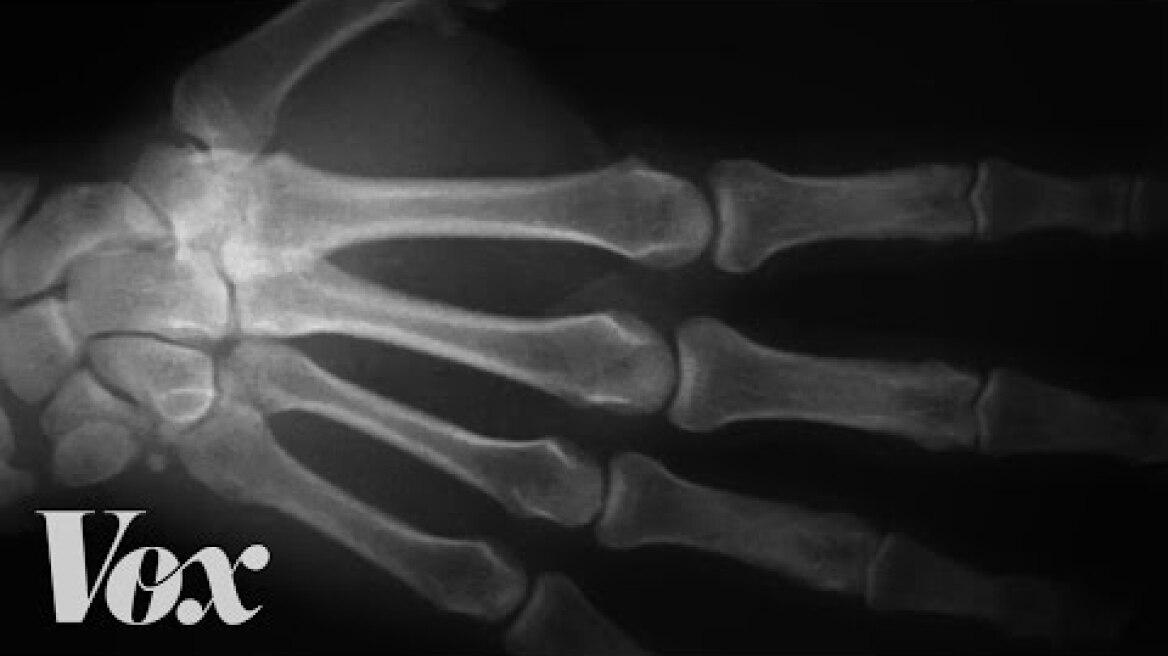

Για να κατανοήσουμε τους πιθανούς κινδύνους του σπασίματος των αρθρώσεων, είναι σημαντικό να καταλάβουμε πρώτα τι συμβαίνει όταν “σπάμε” τις αρθρώσεις μας. Ο ήχος που ακούγεται όταν τσακίζουμε τα δάχτυλά μας είναι το αποτέλεσμα των αλλαγών στην πίεση μέσα στο αρθρικό υγρό, ένα λιπαντικό που βρίσκεται στις αρθρώσεις μας. Αυτές περιβάλλονται από μια κάψουλα γεμάτη με αυτό το υγρό, το οποίο μειώνει την τριβή μεταξύ των οστών και βοηθά στην ομαλή κίνηση. Όταν τραβάμε ή λυγίζουμε τα δάχτυλά μας, ουσιαστικά τεντώνουμε την αρθρική κάψουλα, η οποία μειώνει την πίεση στο εσωτερικό της. Αυτή η πτώση της πίεσης προκαλεί τη δημιουργία φυσαλίδων στο υγρό από αέρια -κυρίως διοξείδιο του άνθρακα, άζωτο και οξυγόνο. Όταν λοιπόν αυτές οι φυσαλίδες εκρήγνυνται, δημιουργούν τον χαρακτηριστικό ήχο «pop» ή «κρακ».

Πρόκειται για μια διαδικασία γνωστή ως «σπηλαίωση» και το ίδιο φαινόμενο συμβαίνει όταν άλλες αρθρώσεις, όπως τα γόνατα ή η πλάτη μας, που παράγουν παρόμοιο θόρυβο. Μετά το αρχικό λύγισμα που κάνουμε, συνήθως χρειάζονται περίπου 20 λεπτά μέχρι το αέριο να διαλυθεί εκ νέου στο αρθρικό υγρό και να μας επιτρέψει να τραβήξουμε ξανά την ίδια άρθρωση.